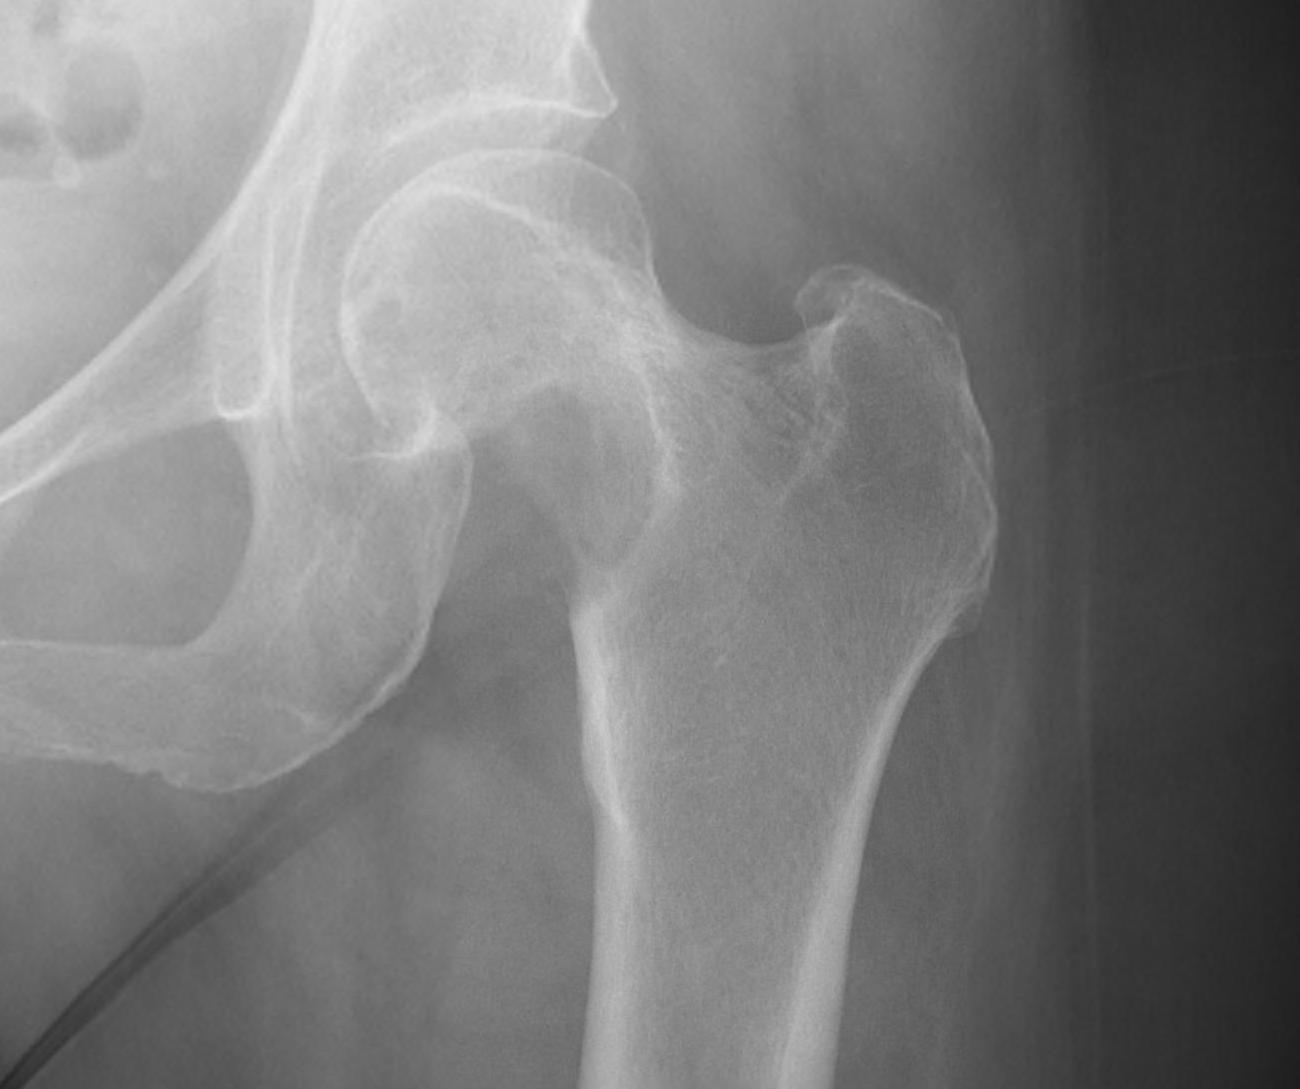

1. Femoral head / neck

- lateral approach

- trans trochanteric

- avoid NV bundle and quadriceps